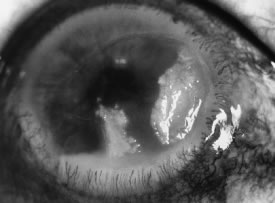

There is no distinguishing clinical sign by which to recognize the genus or species of the infectious filamentous fungus. F. solani is the most virulent organism and typically produces rapidly progressive infection characterized by epithelial and stromal ulceration, dense stromal necrosis, abundant cellular infiltrate, and edema in the adjacent stroma and hypopyon (Figs. 8 and 9). Delicate feathery components are transient. Individual hyphal fragments are rarely visualized. Infection by certain species of Aspergillus and Scedosporium (Figs. 10 and 11) resembles F. solani keratitis and progresses rapidly. Infection by less virulent organisms, such as Curvularia and Alternaria species, produces small, focal (less than 3-mm diameter) areas of nonnecrotizing stromal inflammation with delicate feathery borders (see Fig. 1 and Fig. 12). Macroscopic pigmentation may develop in keratitis caused by Alternaria, Curvularia, and other dematiaceous fungi (Fig. 13).4,11,14 The central component may progress to dense, opaque, gray-white suppuration in the deep stroma without enlargement in total area and may be accompanied by mild inflammation in the adjacent stroma. Iritis is minimal to moderate. Infection caused by other, relatively less virulent organisms resembles herpes simplex or noninfectious keratitis (Fig. 14).

Advanced, severe filamentous fungal or yeast keratitis is indistinguishable from keratitis caused by virulent bacteria such as Staphylococcus aureus or Pseudomonas aeruginosa. The area of epithelial and stromal ulceration is large. Dense, opaque, homogenous, yellow-white stromal necrosis develop and is surrounded by confluent cellular infiltrate and full-thickness stromal edema (Figs. 19, 20, 21). Hyphal elements may penetrate Descemet's membrane and endothelium and be visualized in the anterior chamber. Fibrinous material accumulates over the endothelium, anterior chamber angle, and iris. Pain is typically severe. Secondary ocular hypertension may ensue. Progressive stromal necrosis leads to corneal perforation and, rarely, consecutive endophthalmitis.